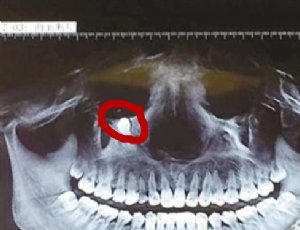

盘点男人女人憋尿的坏处盘点男人女人憋尿的坏处>> 阅读全文 蹚水出行易患丹毒皮肤病蹚水出行易患丹毒皮肤病>> 阅读全文 被老鼠咬到后会怎样被老鼠咬到后会怎样>> 阅读全文 女性患上宫颈癌的早期症状女性患上宫颈癌的早期症状>> 阅读全文 女性须知宫颈癌的早期症状女性须知宫颈癌的早期症状>> 阅读全文 2016三伏天养生应该怎样做2016三伏天养生应该怎样做>> 阅读全文 怀孕早期不能做什么怀孕早期不能做什么>> 阅读全文 怀孕几周后可以检测出来怀孕几周后可以检测出来>> 阅读全文 调味品蒜葱姜辣椒的作用调味品蒜葱姜辣椒的作用>> 阅读全文 专家教你假盐的鉴别方法专家教你假盐的鉴别方法>> 阅读全文 科普吃野生菌中毒的症状科普吃野生菌中毒的症状>> 阅读全文 中医开方治洪涝病 夏季祛湿是关键中医开方治洪涝病 夏季祛湿是关键>> 阅读全文 为什么隔夜西瓜不能吃为什么隔夜西瓜不能吃>> 阅读全文 枸杞的功效和作用 女性食用枸杞的好处枸杞的功效和作用 女性食用枸杞的好处>> 阅读全文 全身斑点成网红 哪些黑痣容易癌变全身斑点成网红 哪些黑痣容易癌变>> 阅读全文 黑色素细胞痣是什么黑色素细胞痣是什么>> 阅读全文 孕期的明显特征有哪些孕期的明显特征有哪些>> 阅读全文 三款消暑食谱降低亲密冲动三款消暑食谱降低亲密冲动>> 阅读全文 过早怀孕宝宝容易夭折过早怀孕宝宝容易夭折>> 阅读全文 未成年人女性怀孕的影响未成年人女性怀孕的影响>> 阅读全文 美女眼眶下长牙 拔牙前注意事项美女眼眶下长牙 拔牙前注意事项>> 阅读全文 夏季消暑好方法煲养生汤夏季消暑好方法煲养生汤>> 阅读全文 王俊凯变北京瘫 葛优躺有危险不可尝试王俊凯变北京瘫 葛优躺有危险不可尝试>> 阅读全文 台风来前要做什么准备台风来前要做什么准备>> 阅读全文 推荐治疗白内障民间偏方推荐治疗白内障民间偏方>> 阅读全文